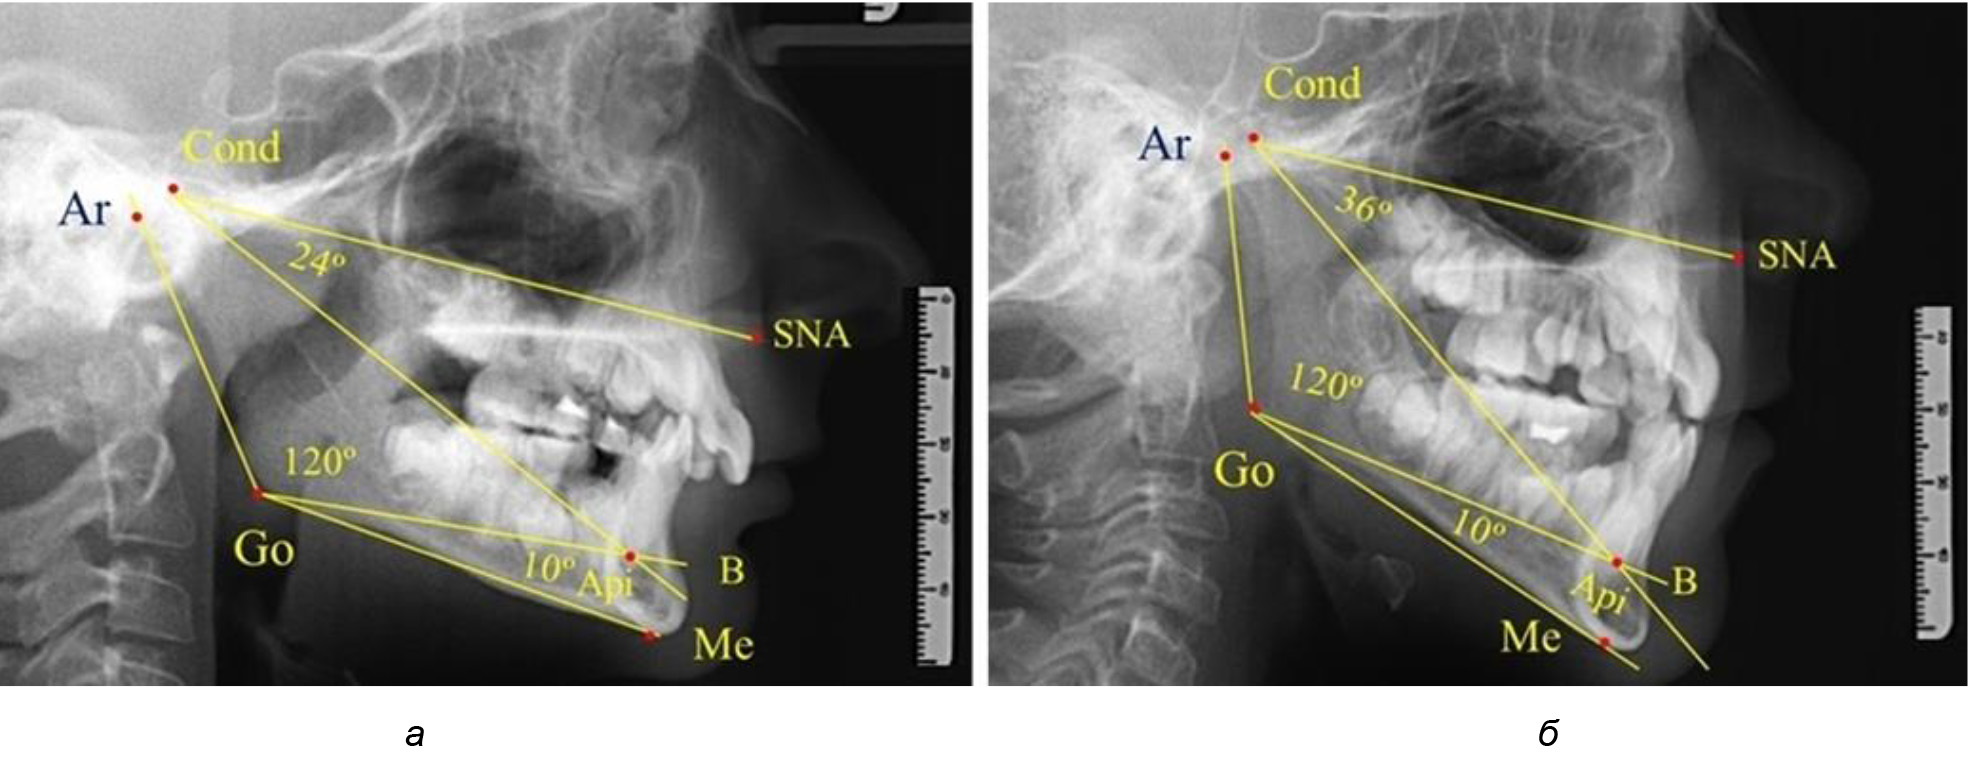

При анализе 16 рентгенограмм с аномалиями окклюзии в вертикальном направлении были выявлены признаки изменения основного гнатического угла. Так, для гнатических аномалий глубокой резцовой окклюзии/дизокклюзии (9 человек) отмечалось уменьшение угла гнатической части лица, величина которого была менее 26°. В то же время для гнатических аномалий (7 человек) вертикальной резцовой дизокклюзии («открытый» прикус) определялось увеличение угла гнатической части лица, который превышал значения в 33° (рис. 7).

Рис. 7. Варианты ТРГ при глубоком прикусе (а) и при открытом прикусе (б)

На представленных клинических примерах, несмотря на различия параметров основного угла гнатической части лица, определялись однотипные варианты угла нижней челюсти Ar-Go-Me и его составных частей Ar-Go-Api и Api-Go-Me.